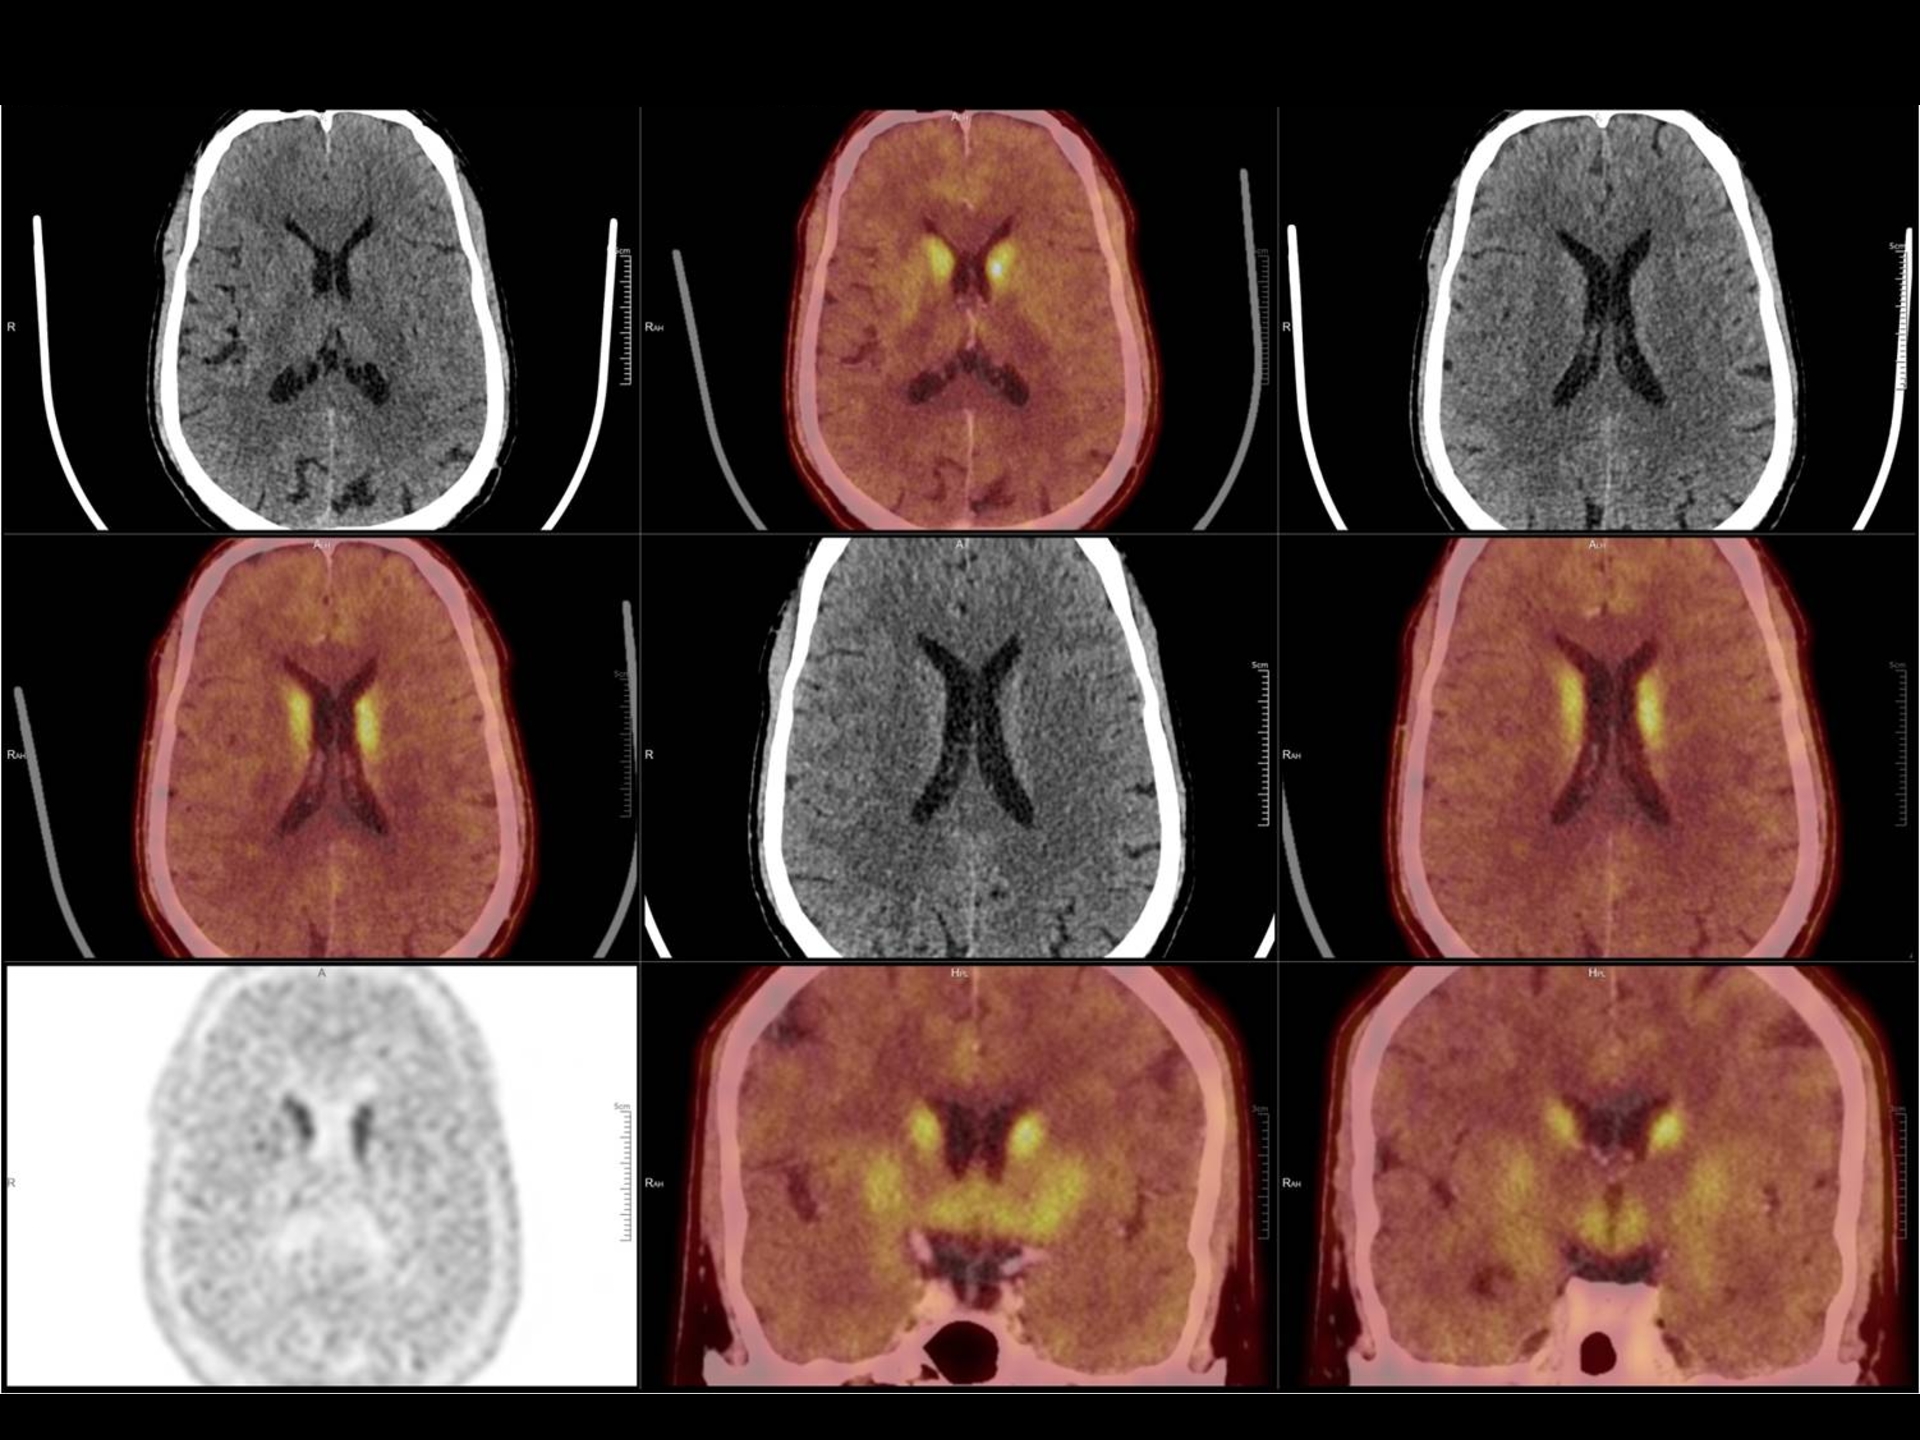

160 Slice Digital Pet-Ct

India’s first 160 slice High Resolution Digital PET-CT provides a revolutionary breakthrough in the combination of clarity, sensitivity, coverage and speed.

Sensitivity of detecting very small lesions (upto size of 5 mm) is very high.

• F-DOPA for Neurodegenerative diseases like early Parkinson’s disease, Alzheimer’s disease and Dementia are also done.